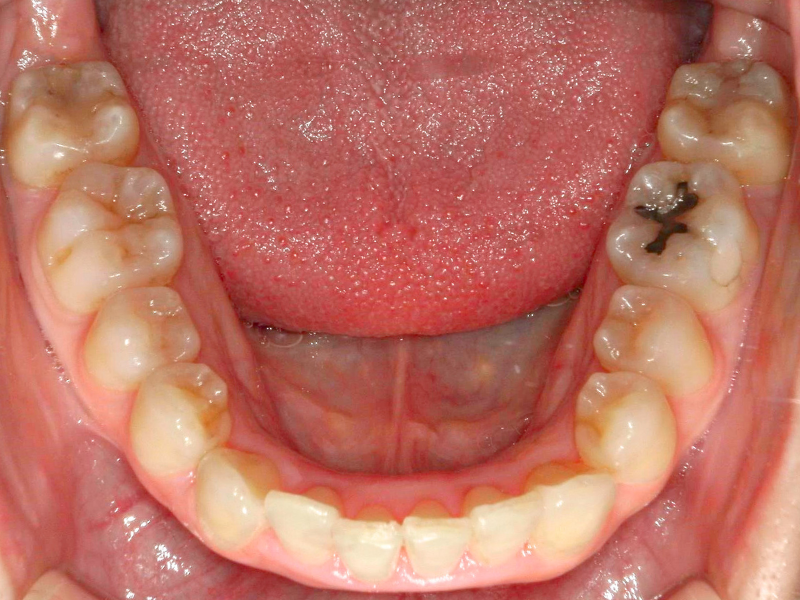

20代、女性、ワイヤー

| 施術内容 | 主訴:下の前歯の凸凹が気になる 詳細:ワイヤー矯正での歯並び改善 |

| 治療期間 | 4ヶ月(10/1現在 治療終了) |

| リスク・副作用 | ■リスク・副作用 ・治療の初期段階では、痛みや不快感が生じやすくなりますが、一週間前後で慣れます。 ・歯の動き方には個人差があるため、予想された治療期間より延長する場合があります。 |

| 費用 | 部分矯正 10万(税込110,000円) |